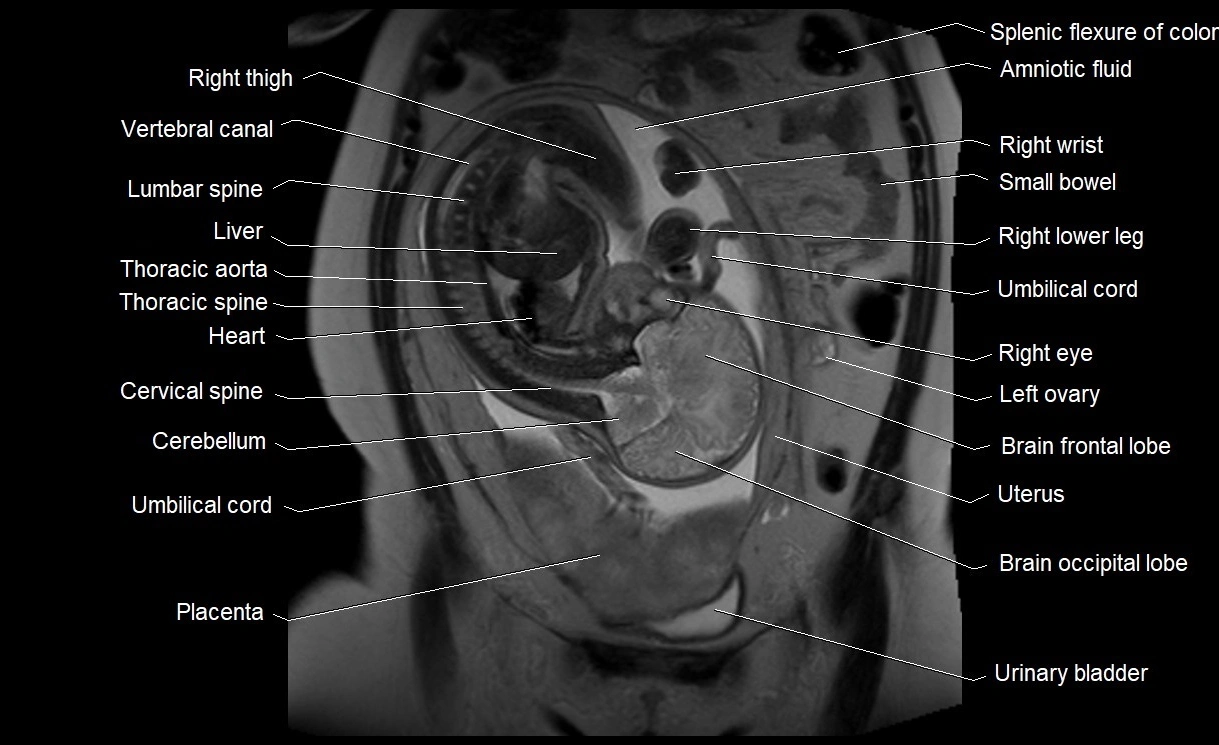

• Imaging relevance: MRI used for fetal visualization and assessing oligohydramnios/polyhydramnios when ultrasound is inconclusive

MRI Appearance

T2 HASTE (T2 GRE):

• Amniotic fluid shows very bright hyperintense signal

• Provides natural contrast against fetus and placenta

• Small particles (vernix) may appear as scattered hypointense foci within bright fluid

MRI image

image